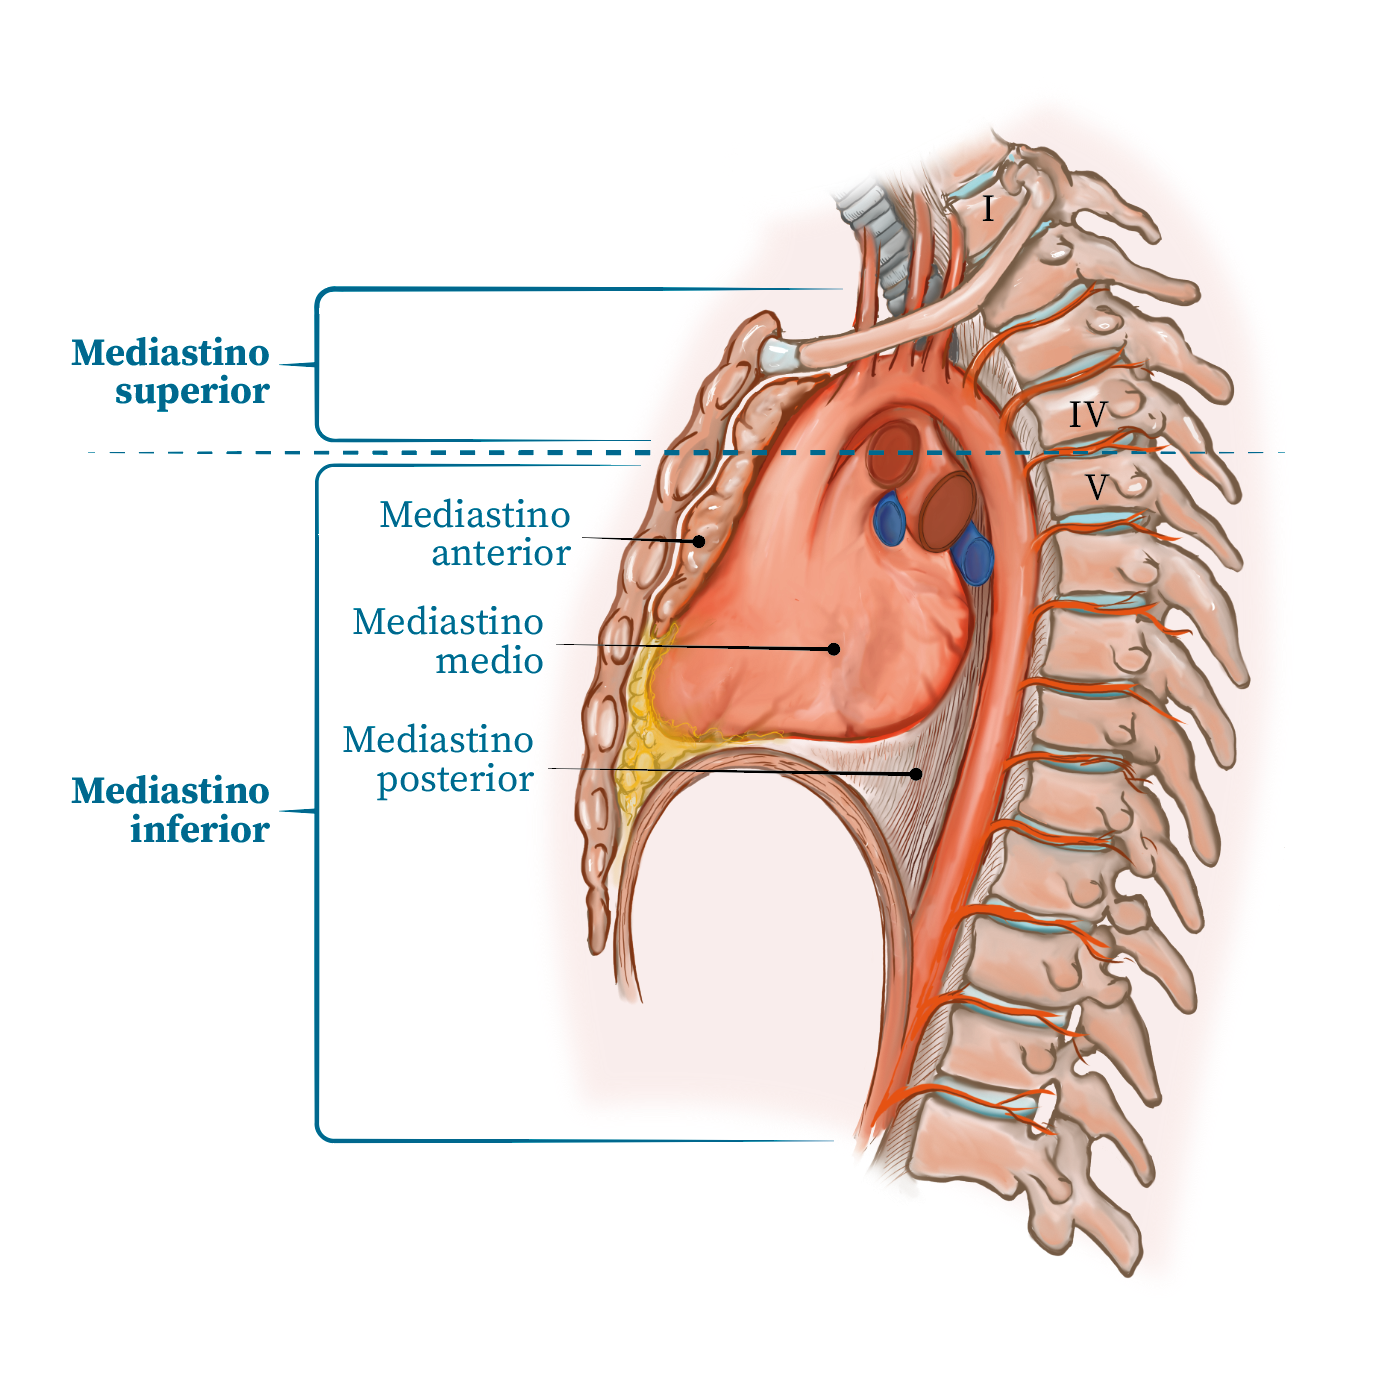

Ilustración médica / Cardiología

Cardiología 2

Cardiología